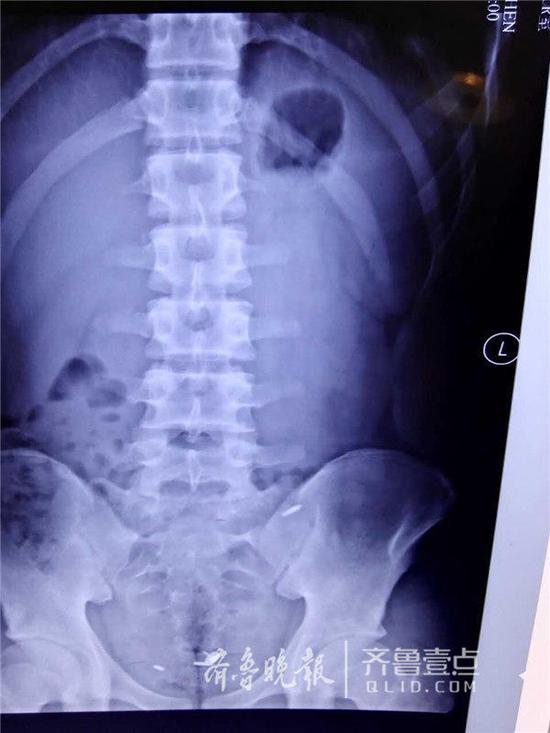

因與同學打賭,濟南一名16歲的少年竟口吞一枚圖釘,並將三個圓珠筆芯頭從肚臍生生塞入腹腔中。事發後,少年被送至山東大學齊魯醫院急救。醫生們經過4個小時的艱難尋找,才通過腹腔鏡將三個圓珠筆芯頭取出,而那枚圖釘也在第二天被幸運地排出體外,整個過程十分驚險。

“非常難找。”李鵬宇說,王川年齡還小,為了減少創傷,他們在王川的肚臍和左右腹部各打了一個小孔,然後通過腹腔鏡進行探查,但沒想到在艱難地找到一個圓珠筆芯頭後就再也找不到了。“由于翻找,筆芯頭一直在換地方,一會在上面,一會在下面;腸子的大網膜、腸間隙非常多,情況復雜。”術中,一度醫生們考慮或許只能通過創傷大的開腹手術將其取出,但考慮到孩子年齡,又堅持了下去。終于,歷經了4個小時的艱難尋找,才終于把三個長1厘米左右的筆芯頭給取了出來。